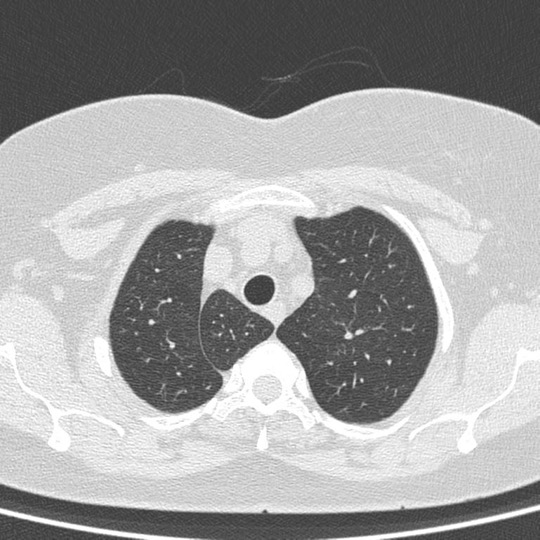

An Azygos lobe fissure is seen on right side. It extends from the lateral aspect of the vertebral body posteriorly, to the right brachiocephalicvein and SVC anteriorly.

• An azygos lobe is a rare normal anatomic variant of the right upper lobe, first described by Heinrich Wrisberg in 1778 due to invagination of the azygos vein and pleura during fetal development.

• An azygos lobe is created when a laterally displaced azygos vein creates a deep pleural fissure into the apical segment of the right upper lobe during embryological development.